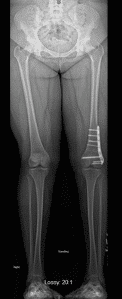

Children who have a knock-knee (valgus) deformity, may require correction of this either with a procedure known as guided growth or with an acute femoral osteotomy. Guided growth uses small plates to tether the growth plate of the femur, allowing the bone to “grow” itself straight over time (Figure 4A). A femoral osteotomy means that the bone is cut and corrected to the new position, then held in this new position while it heals either with a plate/screw construct or with an external fixator (Figure 4B).

Figure 4: (A) This is an 11 year old female with mild knock-knee knee deformity which was treated with growth modulation. This is useful in children with mild deformities who still have open growth plates. As the bone grows, the plate acts like a rubber band and allows the bone to gradually grow straight. (B) A mature adolescent with the same deformity. She was not a candidate for growth modulation because her growth plates were closed so she underwent an osteotomy with a plate and screws.

4A

4B